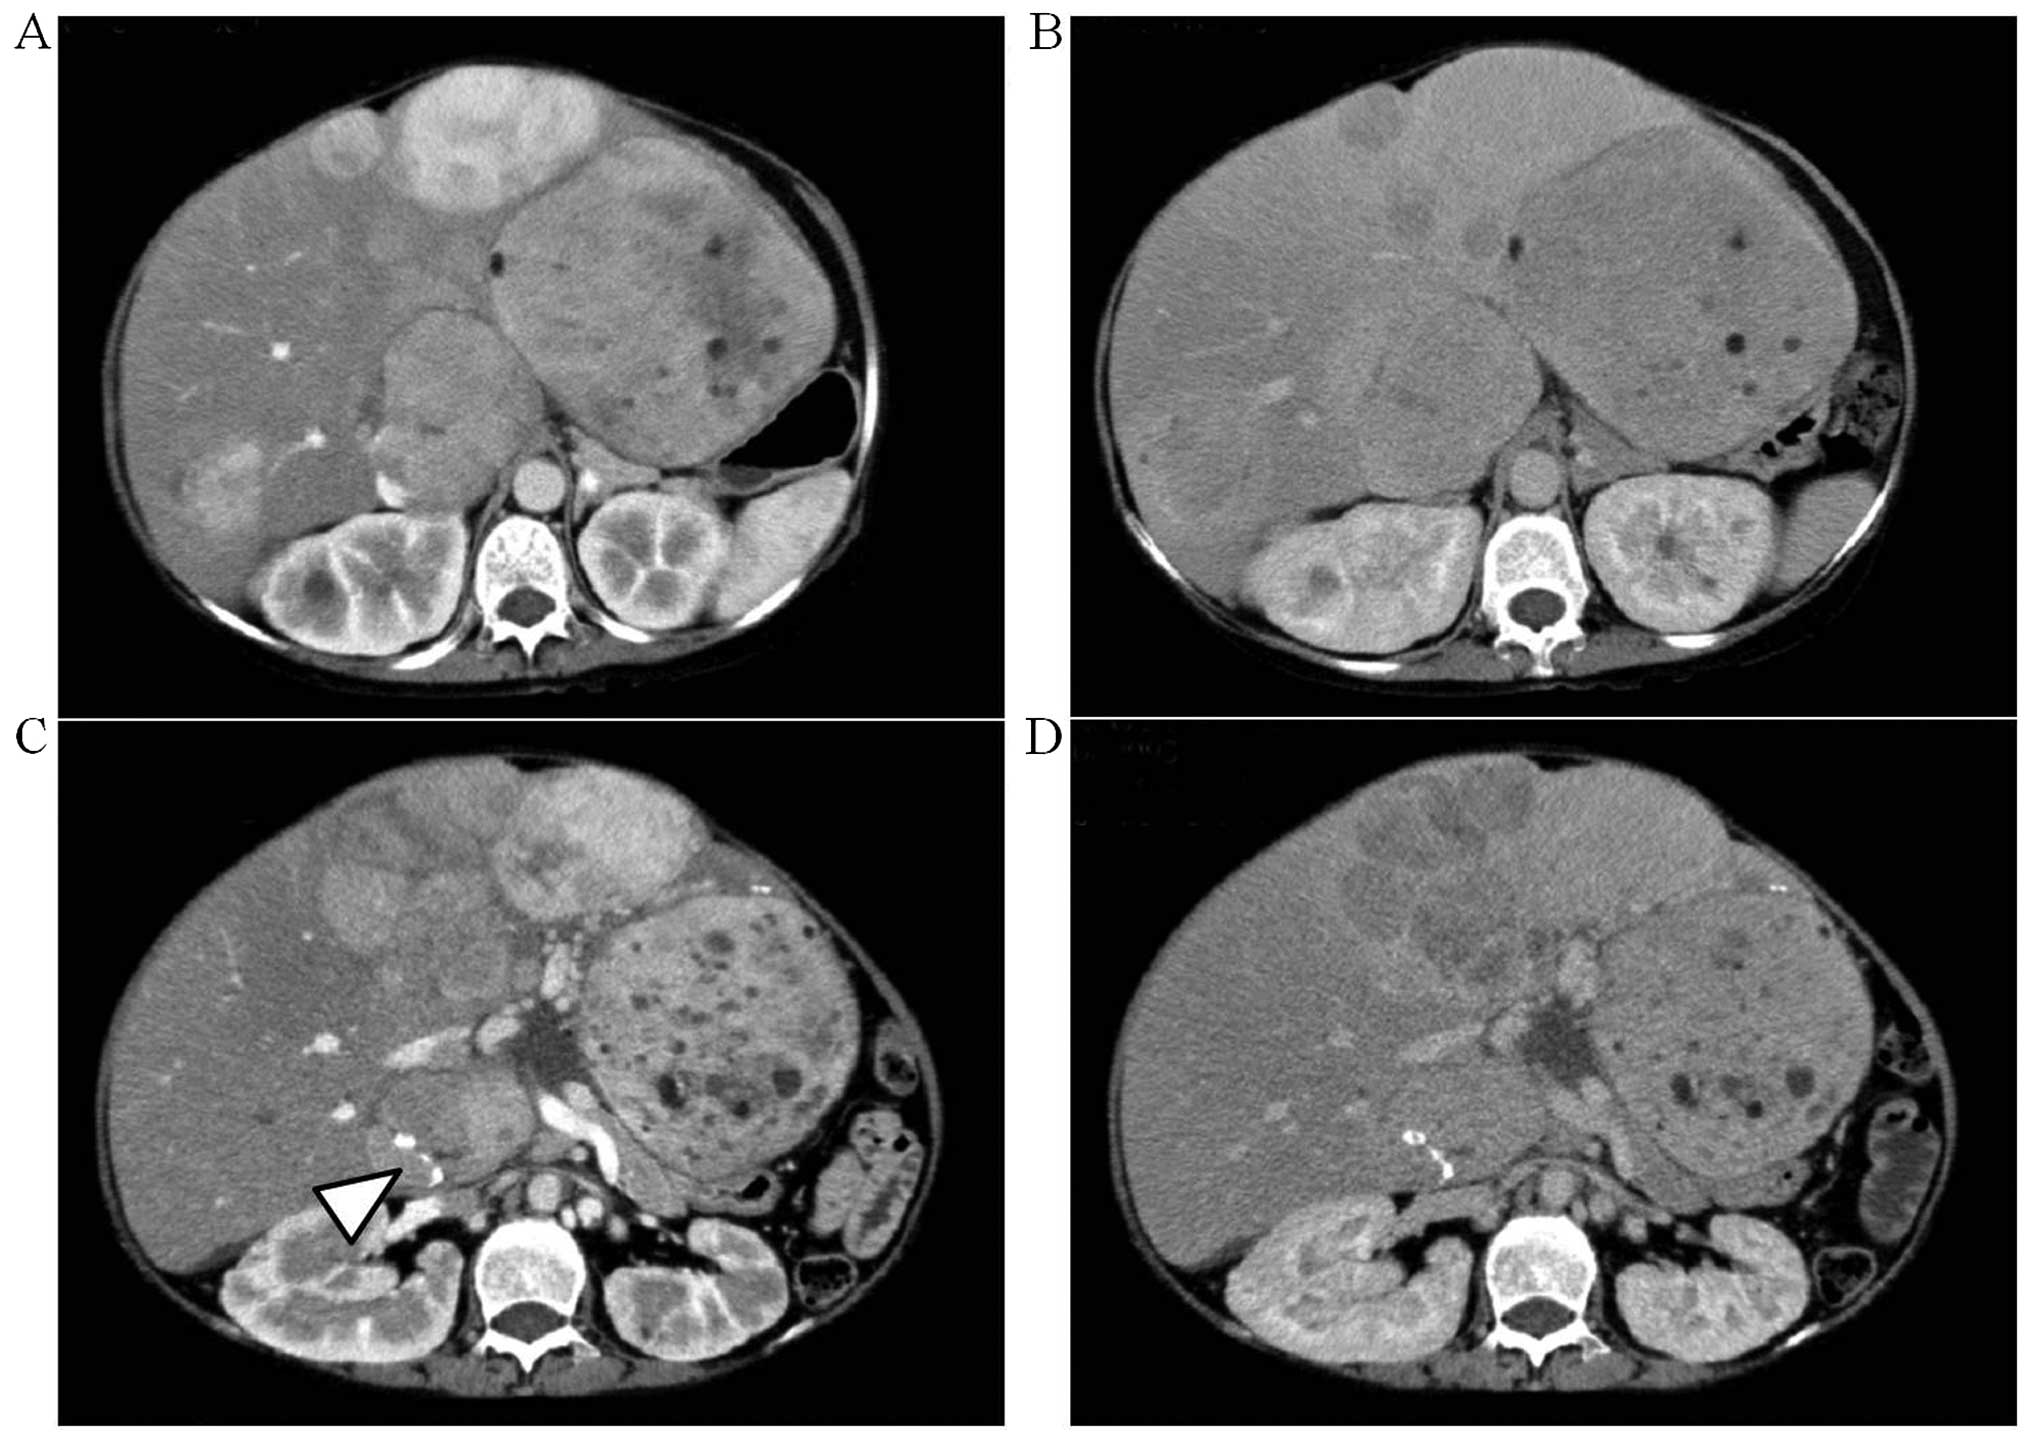

A computed tomography (CT) examination at the first consult revealed relatively well-circumscribed tumors of various sizes (Fig. 2A and B) exhibiting heterogeneous enhancement during the early phase. During the delayed phase, some of the tumors in the lateral segment or the right hepatic lobe exhibited isodensity or low density compared with the surrounding liver parenchyma, whereas the small tumors in the medial segment exhibited low density. These imaging findings were compatible with the characteristics of HA. The size and number of tumors in the medial segment had significantly increased when compared to the CT from 33 months earlier (Fig. 2C and D). In addition, calcification was found in the tumor of S1.

Figure 2.

Computed tomography (CT) scans taken (A and B) at the first consult and (C and D) on the preoperative day. (A and C) Early-phase and (B and D) delayed-phase tumors. The size and number of tumors in the medial segment had increased significantly and calcification was found in the tumor of S1 (arrowhead).